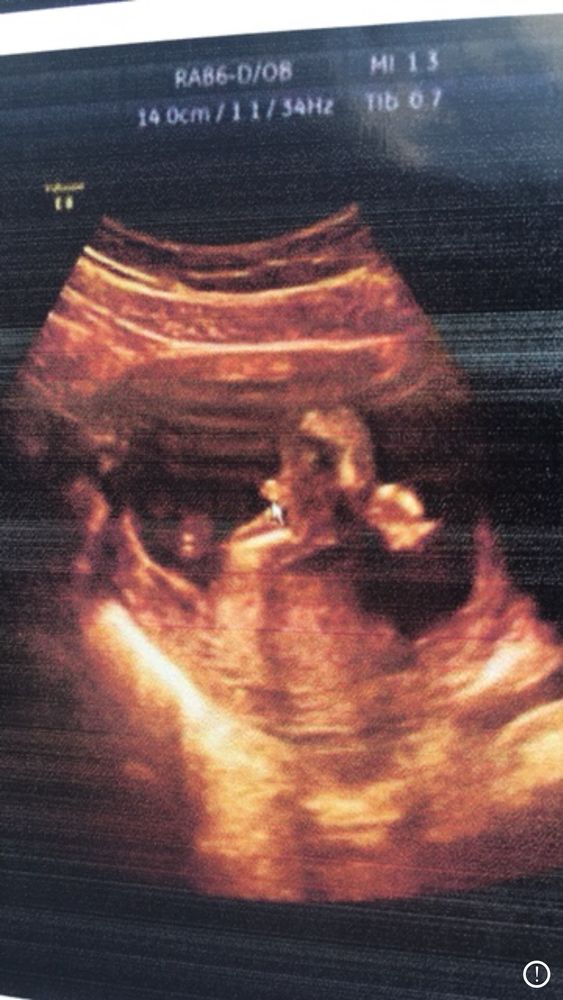

Результаты: УЗИ, КТГ, доплера, скринингаВот по такой фотке на узи определили , что мальчик) он здесь как бы сидит, а там где указатель его пипирка))) похоже ли? Что скажете ?

На фото как-то мало понятно, но, вроде, похоже на писюн😊